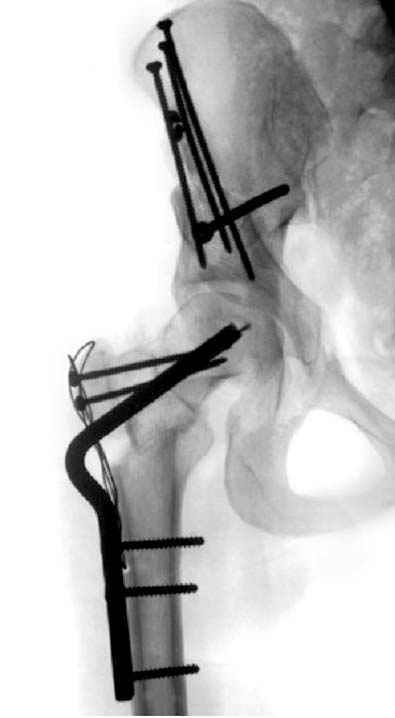

Рис.2 Та же трехмерная модель тазобедренного сустава без аналога связки головки бедра. Пружина динамометра удерживает тазовую часть модели от опрокидывания, поддерживая стабильность так же, как отводящие мышцы обеспечивают ее в отсутствии связки головки бедра.